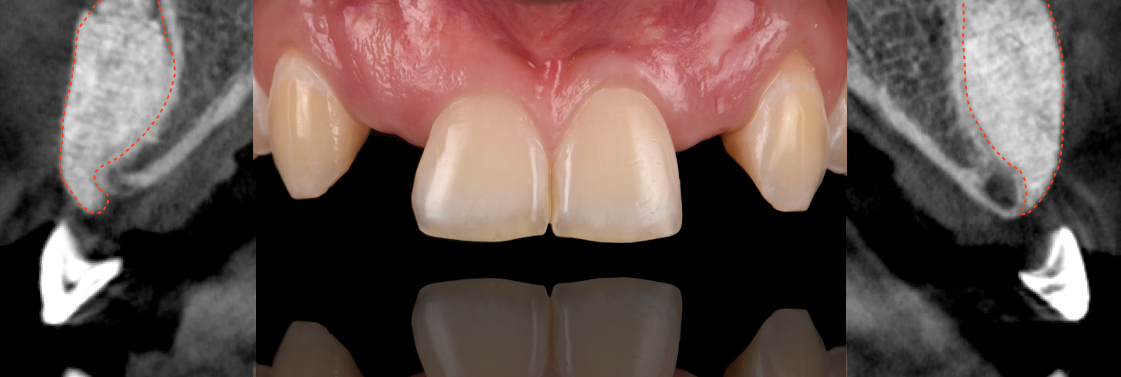

Patient with congenitally missing lateral incisors. The S.M.A.R.T. minimally invasive bone grafting technique provides predictable horizontal bone augmentation with fewer complications, less pain and swelling. S.M.A.R.T. bone graft was performed on both lateral incisor sites using a single incision.

The S.M.A.R.T. approach facilitates flapless implant placement, which may be followed by delivery of a temporary restoration. This results in fewer procedures compared to traditional techniques. Treatment duration is decreased, with less discomfort and less expense to the patient, while preserving soft tissue architecture.

S.M.A.R.T. bone graft helps to enhance the esthetic appearance of implant restorations. The presence of sufficient bone volume makes ideal implant placement possible, facilitating natural restorative contours and emergence profiles.